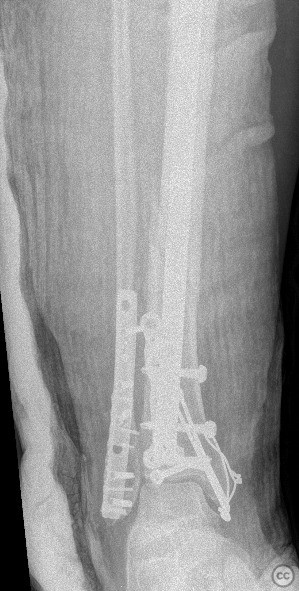

Clinical and radiological findings:  A 45-year-old male sustained a high-energy trauma resulting in an ipsilateral closed tibial shaft fracture and a trimalleolar fracture of the ankle. Initial radiographs demonstrated a displaced mid-diaphyseal tibial fracture (AO/OTA 42-A3) and a trimalleolar ankle fracture (AO/OTA 44-C1), with involvement of the medial malleolus, lateral malleolus, and posterior malleolus. No evidence of open injury or neurovascular compromise was present on examination.

Planning remarks:  The preoperative plan included a staged approach: initial stabilization of the tibial shaft fracture with an intramedullary nail via an infrapatellar approach, followed by open reduction and internal fixation of the trimalleolar ankle fracture through separate medial and posterolateral incisions.

The combination of ipsilateral tibial shaft and trimalleolar ankle fractures presents technical challenges in maintaining alignment and stability during fixation. Sequential fixation allowed for restoration of tibial length and rotation prior to addressing the articular surface of the ankle. Careful soft tissue handling was required due to the proximity of multiple incisions. Stable fixation of all malleolar fragments was achieved with lag screws and neutralization plating as indicated.

Orthopaedic implants used:   tibial intramedullary nail; 3.5mm tubular plate; 4.0mm cannulated screws; mini plate, k wire, cerclage